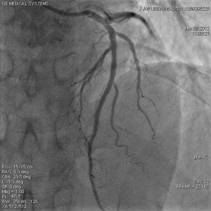

ステント挿入後

急性の心筋梗塞・くも膜下出血・脳梗塞・動脈出血などに対応するアンギオ装置です。

24時間いつでも対応しております。